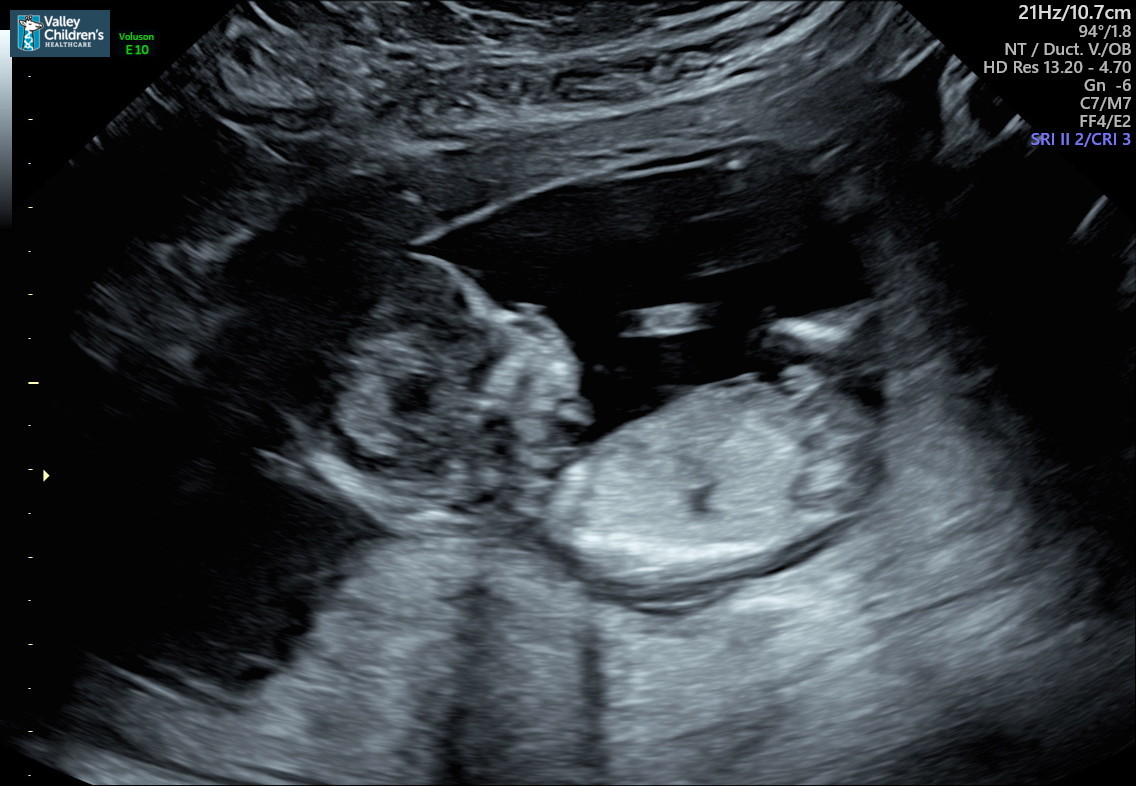

Hello all me and my wife are pregnant with our second and we’re on the fence and can’t tell if a boy or girl?? Any help would be appreciated these pictures will be from 12W 4D, thanks in advance:)Attachment 41451Attachment 41452